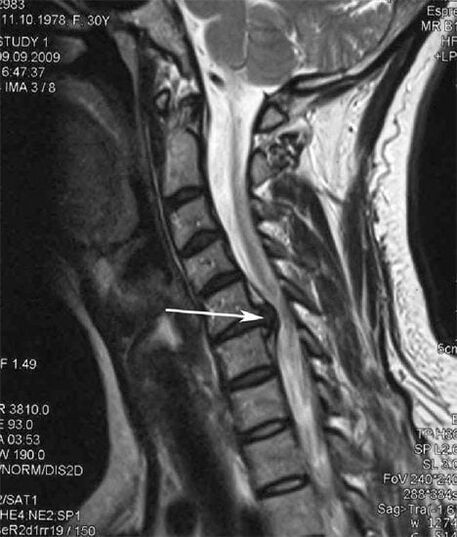

საწყის ეტაპზე ოსტეოქონდროზის გამოვლენა ხდება MRI-ს გამოყენებით. მოგვიანებით, პათოლოგიის დიაგნოსტირება შესაძლებელია რენტგენოგრაფიის გამოყენებით. საშვილოსნოს ყელის ხერხემლის რენტგენოგრაფიაზე შესამჩნევი ხდება ხერხემლიანებს შორის მანძილის დაქვეითება, ფაზის სახსრების პათოლოგიური ცვლილებები და ოსტეოფიტოზი.